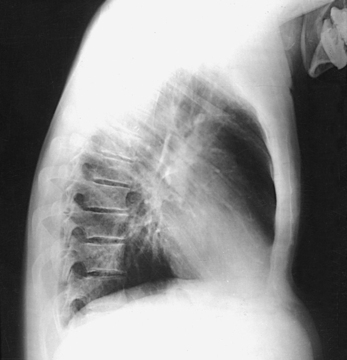

Structures shown: The preliminary left lateral chest position is used to show the heart, the aorta, and left-sided pulmonary lesions (Figs. 10-37 and 10-38). The right lateral chest position is used to show right-sided pulmonary lesions (Fig. 10-39). These lateral projections are employed extensively to show the interlobar fissures, to differentiate the lobes, and to localize pulmonary lesions.

Fig. 10-38 A, Left lateral chest. B, Right lateral chest on same patient as in A. Note the size of the heart shadows.